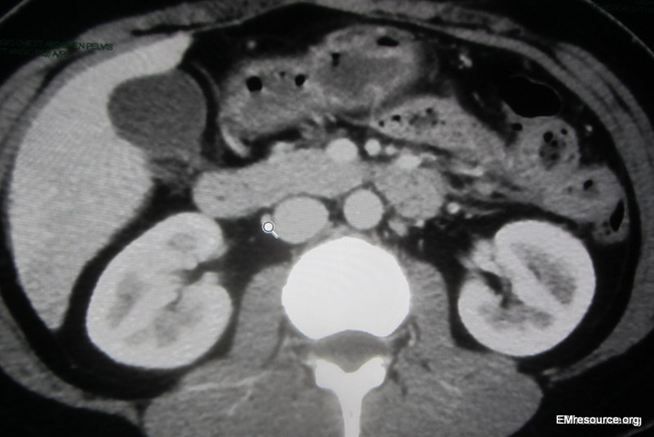

Figure 1. CT chest (click image to enlarge)

The CT scan is read by the radiologist as negative for pulmonary embolism (PE) or any other pathology. A slice of the CT is shown in the Figure 1 (click image to enalrge) and demonstrates a subtle diagnostic finding that was missed by the radiologist.

What is the finding? What is the diagnosis? ANSWER: The CT scan shows subtle increased flow to the liver capsule (see zoomed-in image in Figure 2). The diagnosis is Fitz-Hugh-Curtis syndrome.

Routine blood work including the CBC and even LFTs are usually completely normal. Inflammatory markers such as the erythrocyte sedimentation rate (ESR) and C-reactive protein (CRP) are often elevated. The D-dimer is also elevated in inflammatory conditions and should be checked when pain is pleuritic or accompanied by dyspnea as pulmonary embolism is often the main condition of the differential diagnosis of FHCS. Multiple imaging studies are often considered or ordered to rule out other conditions. The following tests will usually be read as normal if ordered: abdominal ultrasound, pelvic ultrasound, chest x-ray, CT chest, and CT abdomen. If the D-dimer is elevated a CT angiogram chest can rule out PE and may show subtle contrast enhancement around the liver, but beware you may have to request extra cuts to get that low and should talk to your radiologist as she/he will often not note this subtle finding unless they are looking for it.